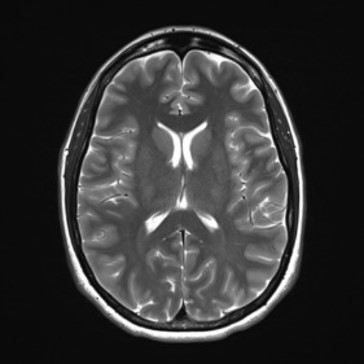

Neuroimaging

All basic MRI for anatomical images (like T2WI, T1WI, GRE, etc), Neuro perfusion, DSC-based perfusion, DCE-based perfusion and permeability, Cerebral blood flow (2D and 3D ASL), Advanced less-distorted DWI, Selective excitement. DTI (B-value ranges from 0 -10000 s/mm2, directions 256) and fMRI (NordicNeuroLab fMRI and Visual system).

Click images for larger view and description

• T2WI